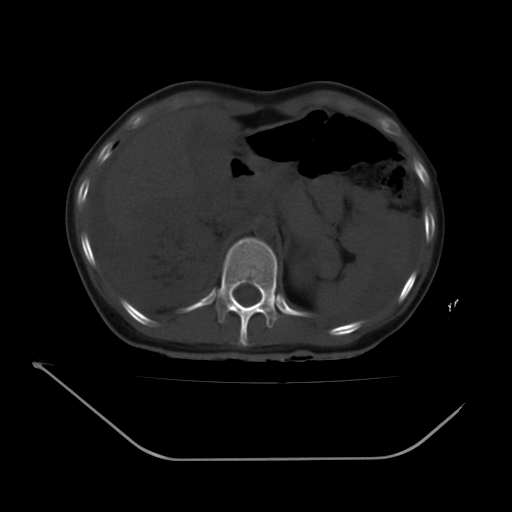

以下是引用liuyue在2008-7-19 13:02:00的发言:[br]1.肝右叶后下段及右肾挫裂伤伴腹腔积血。[br]2.右侧多发性肋骨骨折、横突骨折、右髂骨骨折伴周围软组织挫伤。[br]3.右侧腰大肌肿胀,并可见低密度影,如为气体,则肠道挫裂伤待除外。

以下是引用zhengfaming在2008-7-19 14:42:00的发言:[br]1.肝右叶后下段及右肾挫裂伤伴腹腔积血。脾脏挫裂伤待排[br]2.右侧多发性肋骨骨折、横突骨折、右髂骨骨折伴周围软组织挫伤。[br]3.右侧腰大肌肿胀,并可见低密度影,如为气体,则肠道挫裂伤待除外